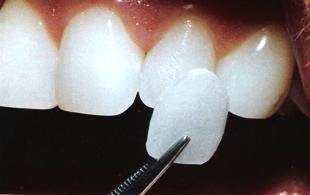

ラミネートベニア

特徴

1. 理想の白さまで最短で近づける

2. 色の後戻りが起こりづらい

3. メンテナンスが楽になる